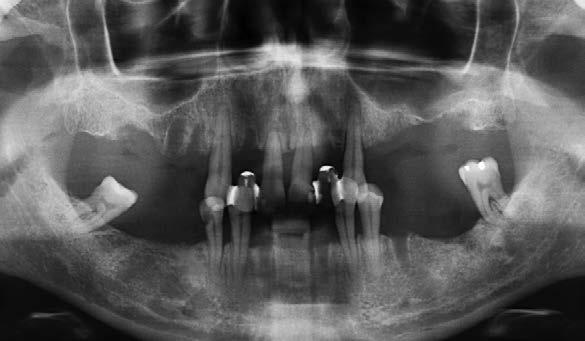

Se presenta el caso de una mujer de 65 años con diagnóstico de periodontitis severa al inicio del tratamiento. El examen clínico evidenció pérdida

Figura 1. Radiografía panorámica inicial que muestra la enfermedad periodontal avanzada de la paciente, con ausencia de varias piezas dentales y otras de mal pronóstico.

ósea vertical generalizada, defectos angulares en sectores posteriores y múltiples ausencias dentarias en ambos maxilares. La inspección intraoral mostró recesiones gingivales, exposición radicular y colapso del tercio anterior como consecuencia de migración dentaria y pérdida de soporte (Figura 1-3).

En la fase inicial del tratamiento se priorizó un enfoque conservador. Se realizaron las exodoncias de las piezas con pronóstico irrecuperable y se procedió a la preservación de los alvéolos mediante PRGF-Endoret, según la técnica descrita por Anitua et al.18 Los dientes remanentes fueron ferulizados temporalmente para servir como provisionales, favoreciendo la estabilidad hasta la colocación de los implantes tras la cicatrización (Figura 4 y 5).

Pasadas 4 semanas, se colocaron los implantes dentales en un momento en que se observaba regeneración ósea incipiente y cierre completo de los tejidos blandos. Tras un periodo

de osteointegración de 6 meses en el maxilar y 3 en la mandíbula, se inició la fase protésica definitiva. En ese momento, la opción preferida fue el uso de pilares personalizados cementados con recubrimiento cerámico. Esta alternativa terapéutica fue la elección para lograr una correcta estética y un sellado adecuado prótesis-implante, con un menor número de complicaciones asociadas. Actualmente, se optaría por una prótesis atornillada, debido a sus ventajas en cuanto a posibilidad de retratamiento, sellado y control de los tejidos.19-21

En la zona anterior maxilar se realizaron pruebas estéticas detalladas, optimizando aspectos como líneas medias, troneras y pónticos (Figura 6-8). En el arco inferior, se conservaron los

caninos y premolares mediante tratamiento periodontal intensivo. Esta decisión favoreció la integración funcional de dientes e implantes, manteniendo la propiocepción y mejorando el control de posibles sobrecargas funcionales como el bruxismo.22-24

La paciente continúa en seguimiento. A los 8 años, la estabilidad de los tejidos duros y blandos, así como la estética de la rehabilitación, era completa (Figura 9-11). A los 12 años se observó

una buena progresión del tratamiento, sin cambios reseñables (Figura 1214). A los 20 años de seguimiento se constató una evolución estable, sin pérdida ósea en dientes ni implantes, y con buena salud de los tejidos periimplantarios (Figura 15-17).